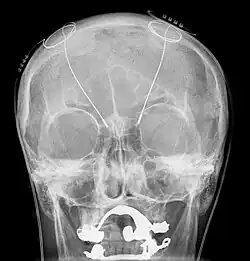

A working diagnosis is made from a neurological examination and evaluation. Parts of a complete examination include a physical examination, magnetic resonance imaging (MRI), patient history, and electrophysiological and accelerometric studies. A diagnosis of solely intention tremor can only be made if the tremor is of low frequency (below 5 Hz) and without the presence of any resting tremors.[1] Electrophysiological studies can be useful in determining frequency of the tremor, and accelerometric studies quantify tremor amplitude. MRI is used to locate damage to and degradation of the cerebellum that may be causing the intention tremor. Focal lesions such as neoplasms, tumors, hemorrhages, demyelination, or other damage may be causing dysfunction of the cerebellum and correspondingly the intention tremor.[14]